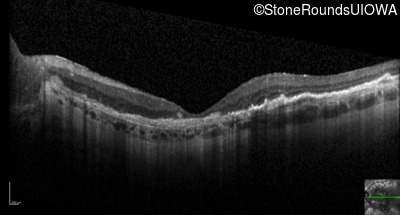

Optical Coherence Tomography - Left - 20/160 -1

Exemplar / OCT Stack

OCT Stack